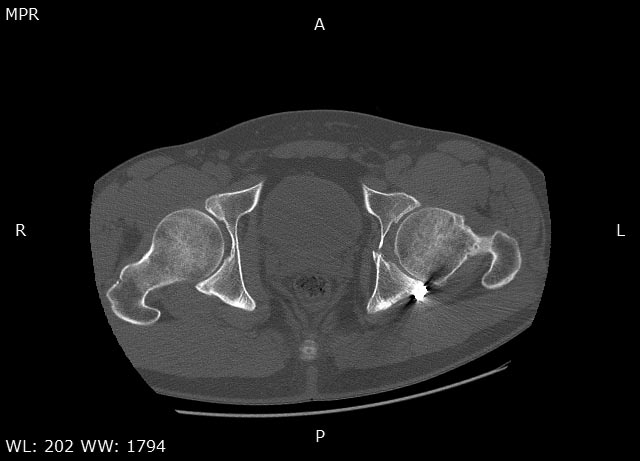

Травма в 2015 году. Водитель, попал в ДТП. Первично повреждение печени, перелом локтевой кости слева. Перелом задней колонный и задней стены левой вертлужной впадины. По экстренным показаниям выполнялась лапаротомия. Синтез задней колонны и задней стены через 13 дней через доступ Кохера-Лангенбека. Гладкий послеоперационный период. Выписан на амбулаторное лечение через 15 дней после операции. После выписки к нам не обращался, так как является жителем другого региона. Обратился через 2,5 года с жалобами на боли в области левого тазобедренного сустава.

На РКТ таза - перелом сросся. Отмечается кисты в области верхнего полюса головки бедра. Пластина фиксирующая задний край соприкасается с задними отделами головки бедра (видимо произошел частичный лизис костного края).